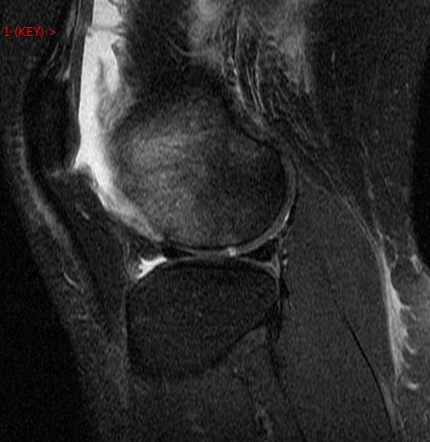

Figure 1 for case Patellar dislocation

Figure 1

Discussion

All the classic findings. Im showing this one because of the loose chondral body knocked off of the patella. Nice example.

Patellar dislocation